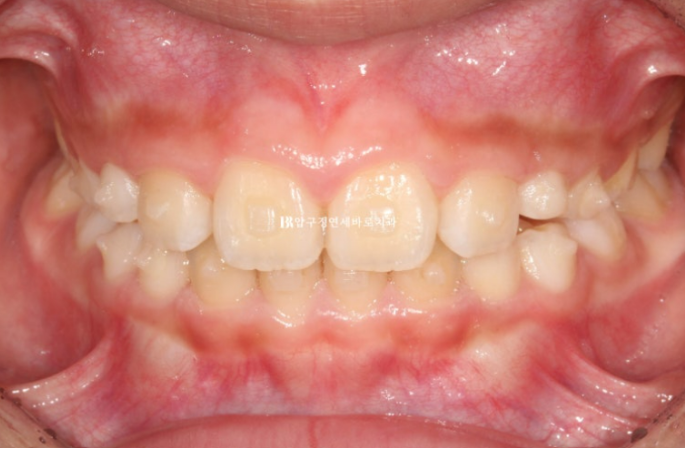

치료 후 사진입니다.

24.01

어금니 교합은 좋으며 그 사이 남아있던 유치가 대거 빠지고 영구치가 새로 나는 중입니다.

송곳니 날 자리를 충분히 마련해주었습니다.